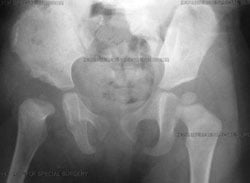

Preoperative view of a right hip dislocation, where the right leg appears shorter than the left.

Anterior-to-posterior (front-to-back) X-ray image, six months after open reduction with a realigned right hip.